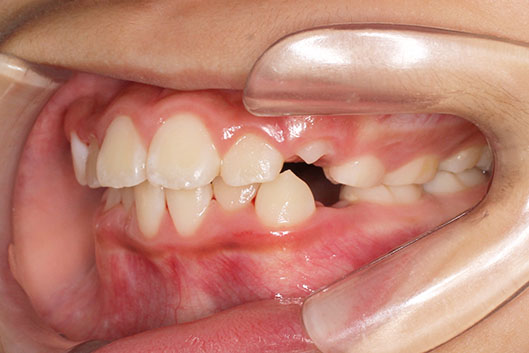

側方歯(犬歯、小臼歯)の生え変わりの時期。 前歯のがたつきを気にされ、小児矯正からの治療を希望されました。 お母様は、矯正治療経験済みですので、治療には前向きで早期治療の必要性を納得されていました。 小児矯正では、永久歯の生え変わるためのスペースを増加させ、がたつきを軽減させることを目的で行います。 残ったがたつきは、全ての永久歯が生え変わってから、本格矯正(マルチブラケット装置での治療)で改善しています。 比較的、叢生量は少ないため、本格矯正は非抜歯にて配列しました。

マルチブラケット 動的治療期間 2年6か月 調整回数16回 特に問題もなく、保定後も安定しています。